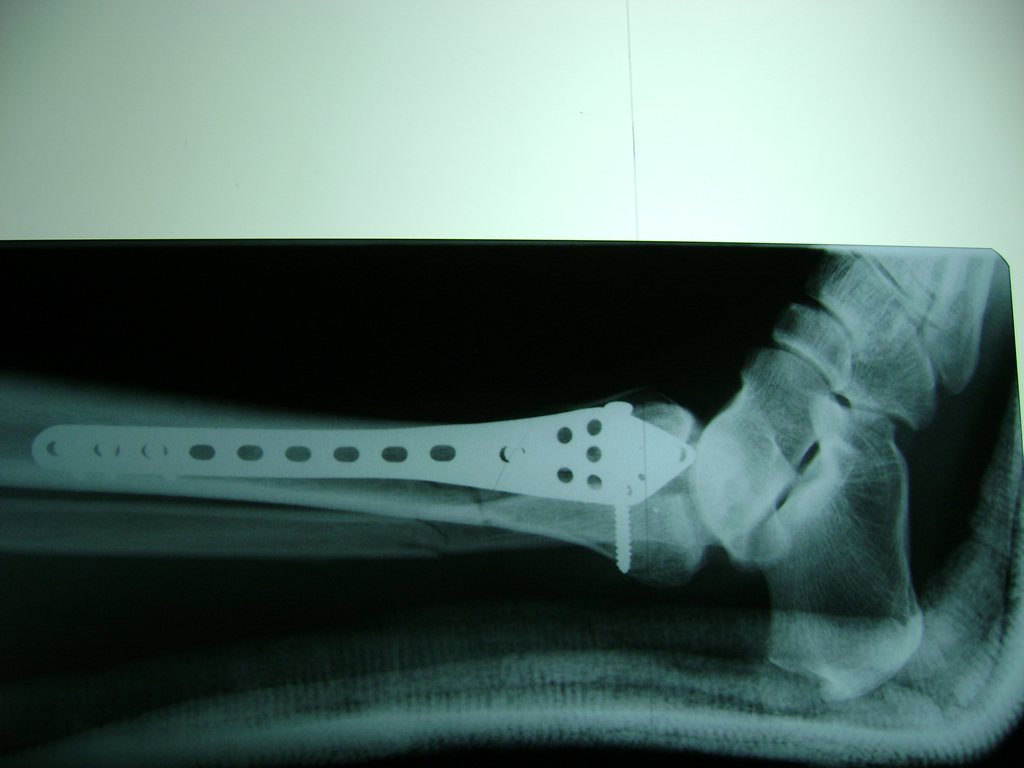

Una fractura de tobillo es la rotura de uno o más de los huesos del tobillo. Estas fracturas pueden ser:

Algunas fracturas de tobillo pueden requerir cirugía si:

- Los extremos de los huesos están desalineados entre sí (desplazados).

- La fractura se extiende hasta la articulación del tobillo (fractura intra-articular).

Cuando se necesita cirugía, es probable que esta implique el uso de clavijas de metal, tornillos o placas para sostener los huesos en su lugar mientras la fractura se consolida. Los elementos de soporte pueden ser temporales o permanentes.